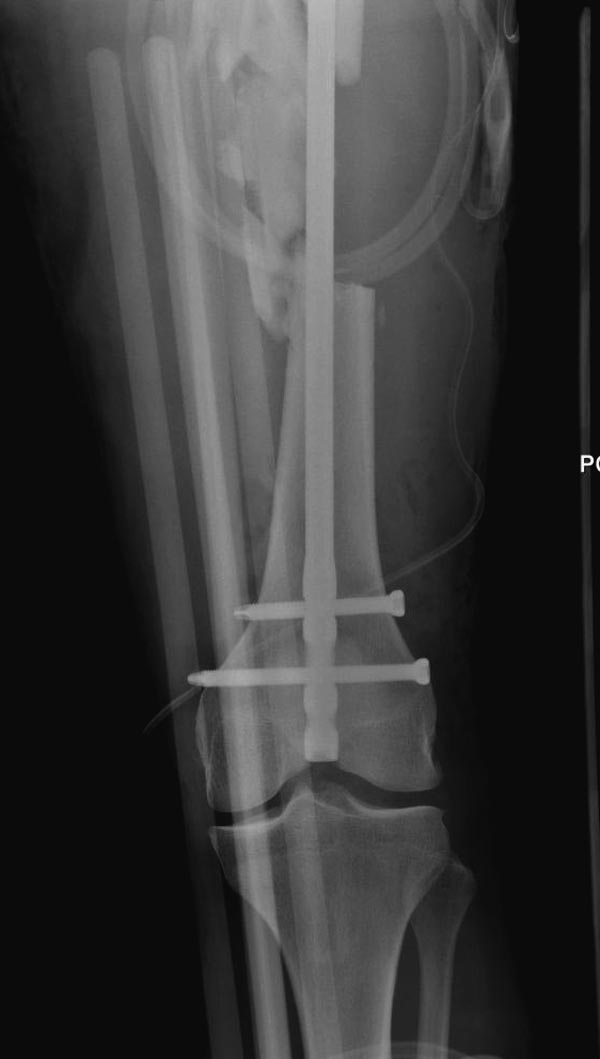

Здесь выставлен ренгенограммы больного, ему 21, травму получил в

результате высокоскоростной погони на украденной машине, которая

закончилась смертью трех остальных“боевых комрадов”. Начатую коллегой

открытую операцию на шейке пришлось закончить мне, установкой винтов и

ретроградной фиксацией бедра. Выписка в обычное сроки и наблюдался

амбулаторно. Каждый раз напоминали о возможности осложнений ввиде

несращения! По истечению 4 месяцев появились признаки варусной

деформации. На СТ срезах несращение шейки и бедра. Риминг, замена на

более толстый гвоздь и вальгусная остеотомия.